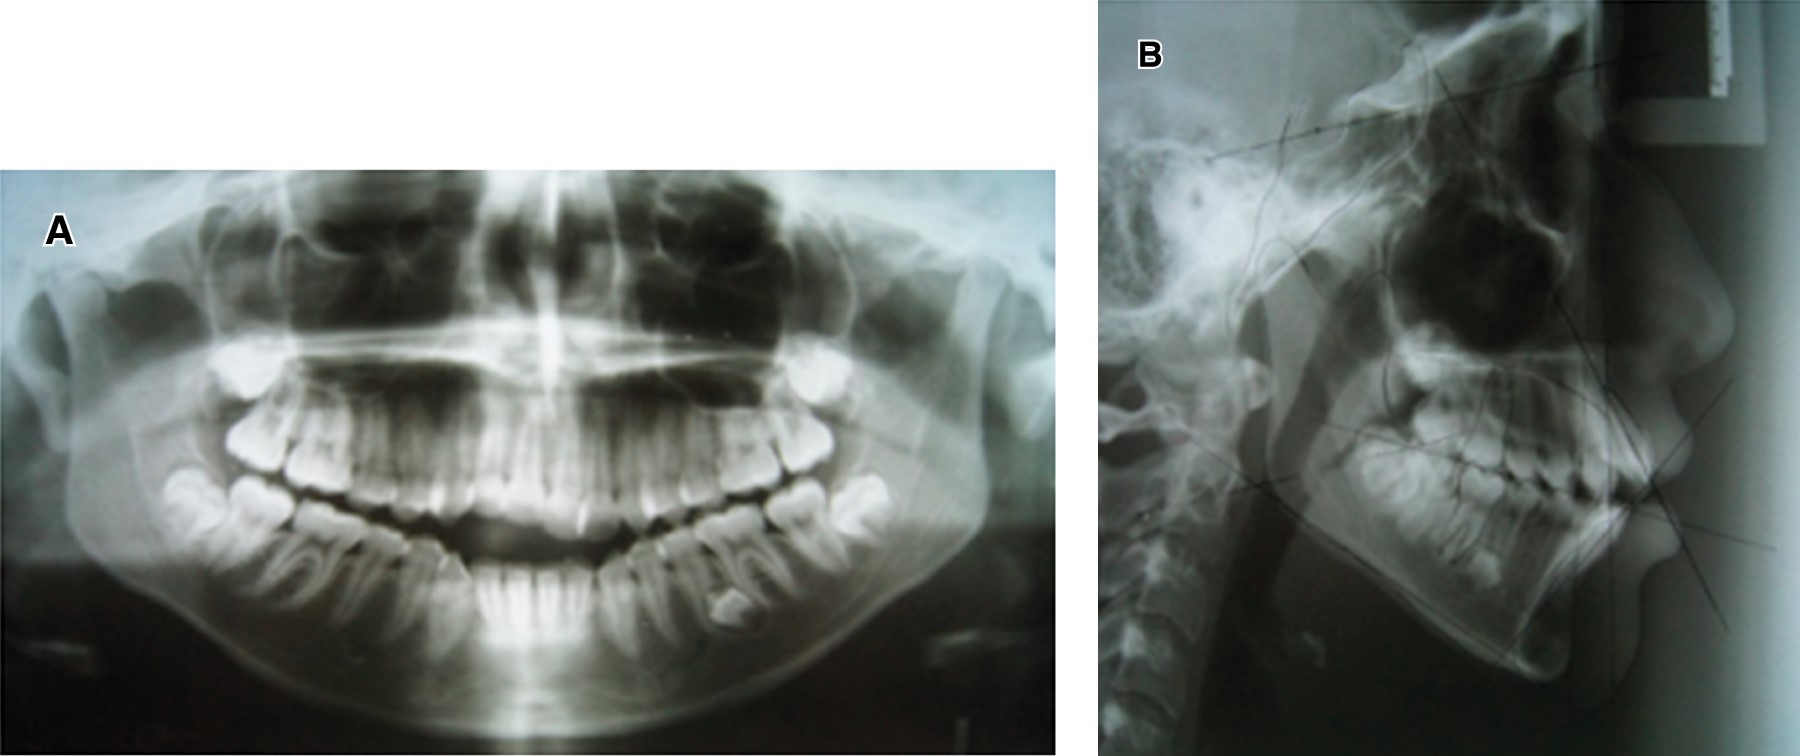

La radiografía panorámica nos muestra la presencia de un diente supernumerario que se encuentra dentro del hueso mandibular del lado izquierdo entre el segundo premolar y el primer molar, el cual va a ser retirado cuando el tratamiento haya concluido; ligero paralelismo radicular, presencia de gérmenes dentarios de los terceros molares superiores e inferiores, como se muestra en la Figura 3A. En la lateral del cráneo (Figura 3B) se utilizó el análisis cefalométrico de Steiner, arrojando un ANB de 5o y GoGn-SN de 45o y un Wits de -6 mm. Con los datos obtenidos se determinó diagnosticar a la paciente como una clase III por hipoplasia maxilar compensada esqueletalmente por el crecimiento vertical de la mandíbula como se muestra en la Tabla 1.

Figura 3